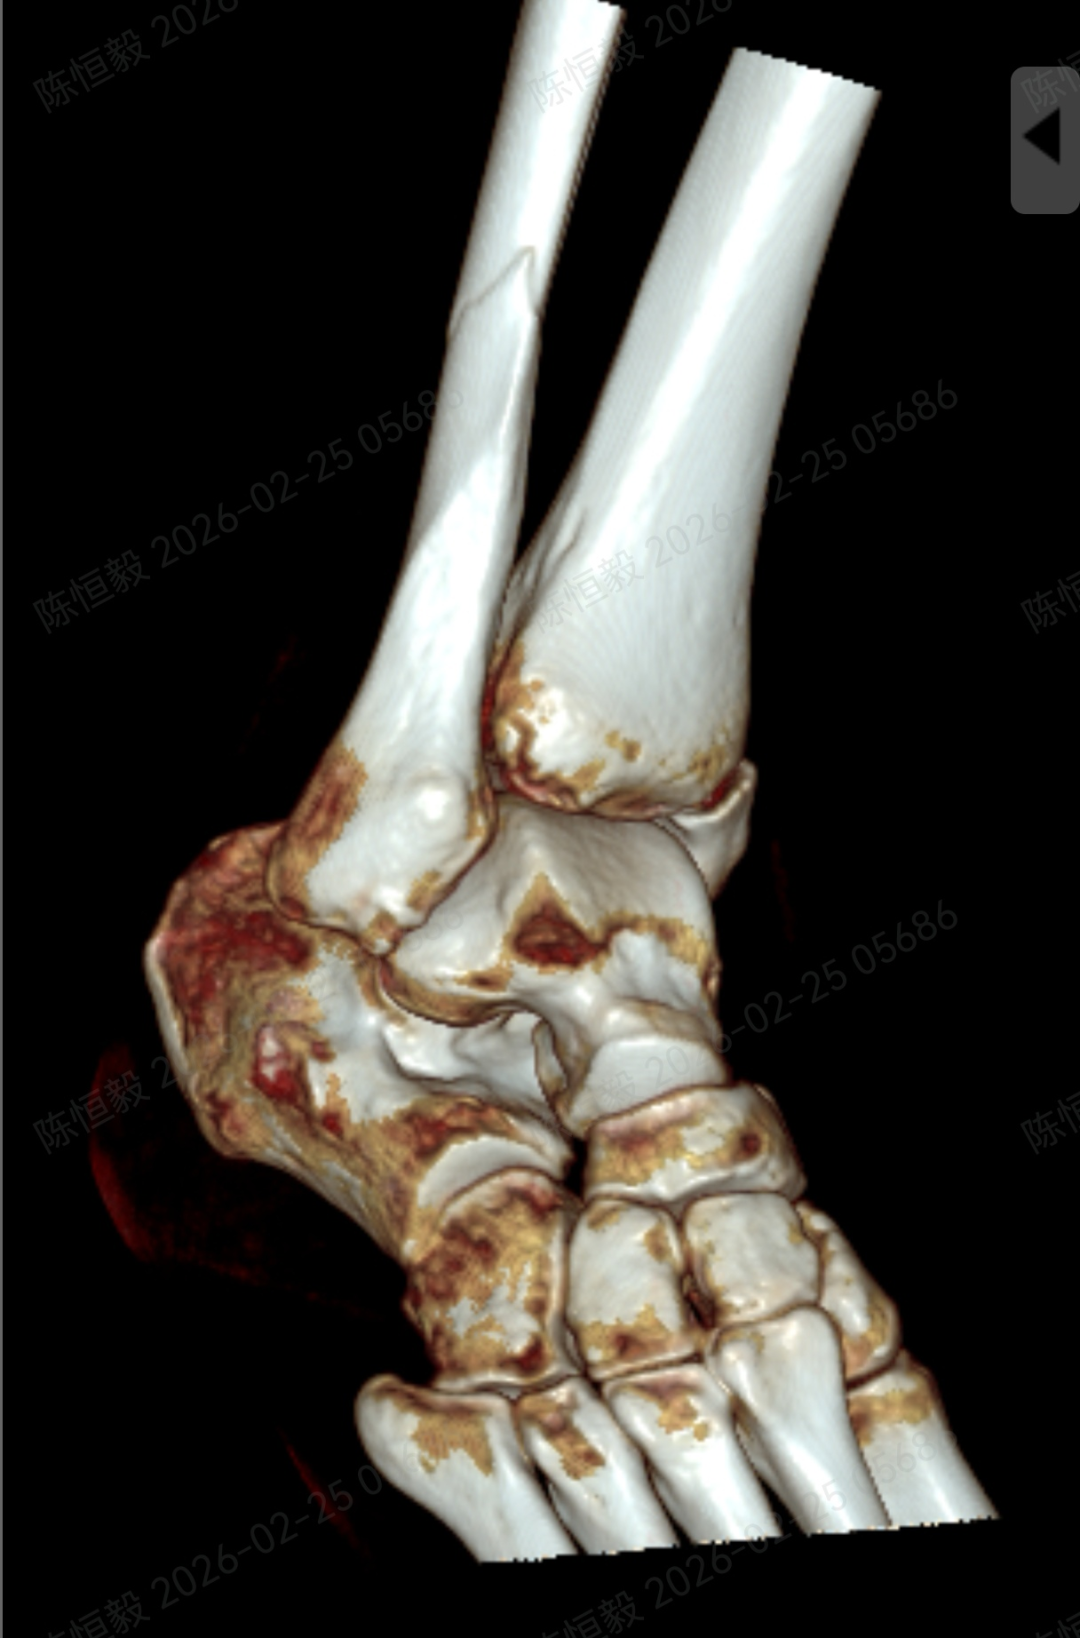

针对王女士的踝关节骨折情况,由副主任医师陈涛主刀,足踝外科团队为其实施了关节镜辅助下机器人导航微创闭合复位内固定术。

通过 5 毫米小切口将关节镜探入关节腔内,清理腔内淤血与致炎因子,清晰观察骨折块移位及关节软骨损伤情况;

在关节镜直视下,使用微创器械将骨折块复位至解剖位置,恢复关节面平整;

依托机器人导航系统,规划螺钉置入通道,避开关节面与重要组织;

最后通过另外两个 5 毫米的小孔置入空心螺钉,完成骨折端的稳定固定。

整个手术仅通过三个 5 毫米的小切口完成,最大程度降低了手术创伤。

对于踝关节骨折的诊疗而言,关节面复位的精准度直接关系到远期恢复效果,若复位存在偏差,可能增加创伤性关节炎、慢性疼痛、关节功能障碍等问题的发生概率。

本次诊疗中,在关节镜直视下确保骨折部位实现解剖复位,同时对检查中发现的合并软骨损伤进行了同步处理,为关节的后续恢复提供了保障。